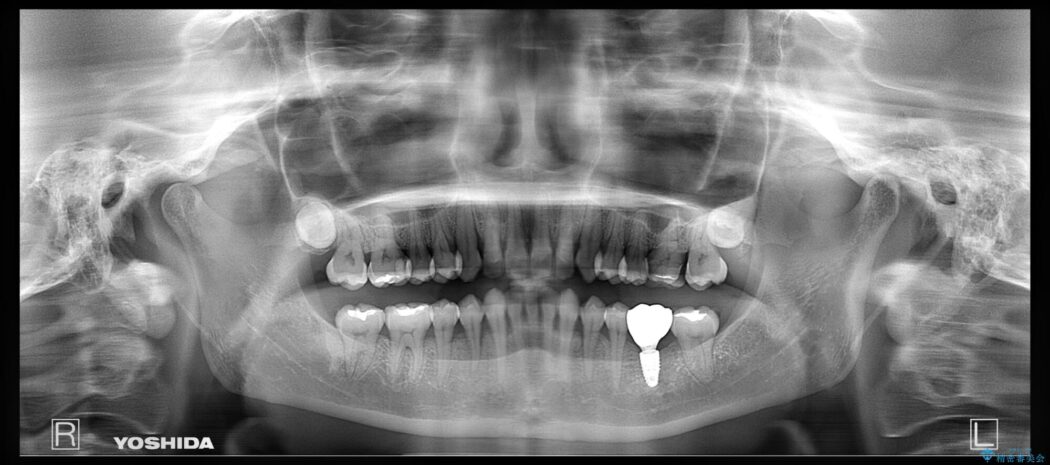

治療計画を立てる上で詳しく精密検査をしたところ、左下の6番目の歯につきまして治療が必要な状態であることが分かり、かぶせ物を外し、内部を確認しました。

結果としては深い部分で根が破折してしまっていました。

破折の処置としては基本的に抜歯が選ばれます。

悪くなっている歯の放置はできないと判断しましたので、患者様と様々な治療プランを相談した上で、最終的に該当の歯は抜歯をして噛み合わせを改善し、その後インビザラインでの矯正治療を行うこととしました。